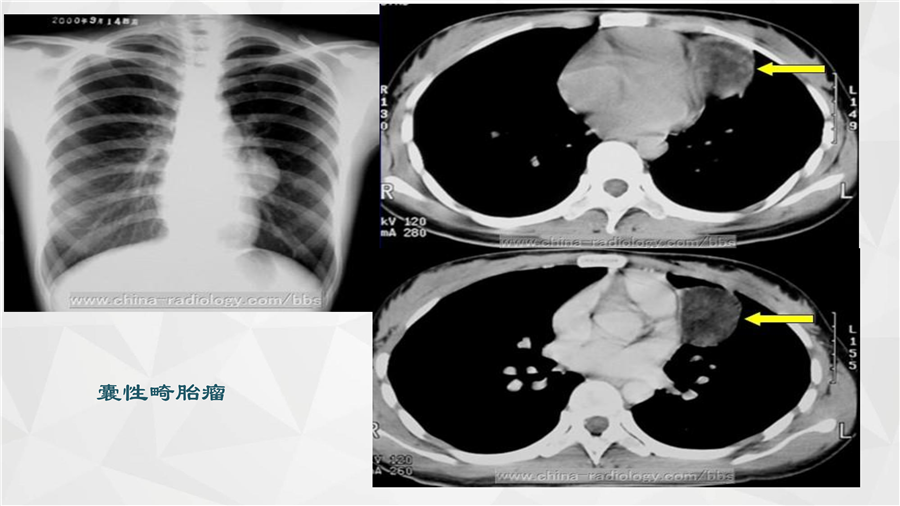

呼吸系统三